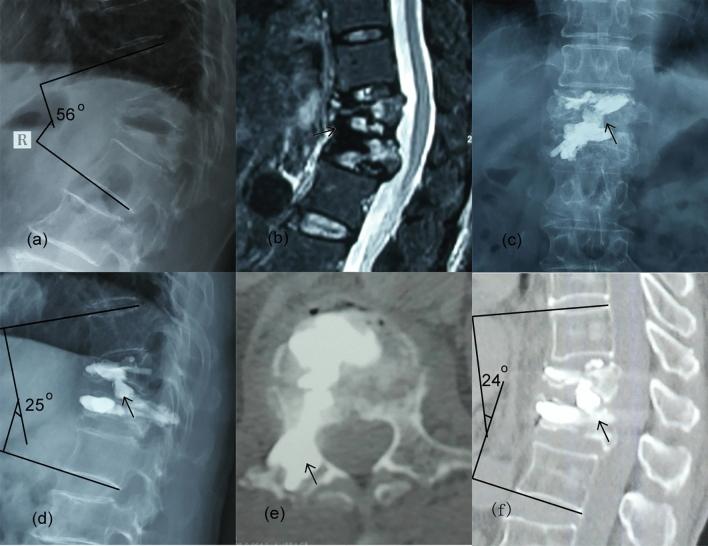

This paper describes a minimally invasive technique of percutaneous intervertebral bridging cementoplasty (PIBC) to augment the fractured vertebrae and immobilize the intervertebral space with endplate-disc complex injury simultaneously. Thirty-two patients with adjacent multilevel osteoporotic thoracolumbar fractures (AMOTLFs) and vertebral endplate-disc complex injury (EDCI) treated by PIBC were retrospectively reviewed. The PIBC technique was a combination of puncture, balloon expansion and bridging cementoplasty. The clinical and radiological assessments were reviewed. The operation time was 82.8 ± 32.5 min, and blood loss was 76.9 ± 31.7 mL. A cement bridge was connected between the two fractured vertebrae across the injured intervertebral space. VAS at three time points including pre-operation, post-operation 1 day and final follow-up was 6.9 ± 0.9, 2.9 ± 0.8 and 1.7 ± 0.8, respectively; ODI at three time points was (71.1 ± 7.8)%, (18.4 ± 5.7)%, and (10.3 ± 5.7)%, respectively; Cobb angle at three time points was 46.0° ± 10.4°, 25.9° ± 8.5°, and 27.5° ± 7.1°, respectively. Compared with pre-operation, VAS, ODI and Cobb angle were significantly improved at post-operation 1 day and final follow-up (P < 0.05). Clinical asymptomatic cement leakage was observed in thirteen patients. No vessel or neurological injury was observed. PIBC may be an alternative way of treatment for AMOTLFs with EDCI. The technique is a minimally invasive surgery to augment the fractured vertebrae and immobilize the injured intervertebral space simultaneously.

本文介绍了一种经皮椎间桥接骨水泥成形术(PIBC)的微创技术,该技术可同时增强骨折椎体并固定有终板-椎间盘复合体损伤的椎间隙。回顾性分析了 32 例经 PIBC 治疗的相邻多节段骨质疏松性胸腰椎骨折(AMOTLFs)和椎体终板-椎间盘复合体损伤(EDCI)患者。PIBC 技术是一种穿刺、球囊扩张和桥接骨水泥成形术的结合。回顾了临床和影像学评估。手术时间为 82.8±32.5 分钟,出血量为 76.9±31.7 毫升。在受伤的椎间隙之间,两个骨折椎体之间形成了一个水泥桥。术前、术后 1 天和最终随访时的 VAS 分别为 6.9±0.9、2.9±0.8 和 1.7±0.8,ODI 分别为(71.1±7.8)%、(18.4±5.7)%和(10.3±5.7)%,Cobb 角分别为 46.0°±10.4°、25.9°±8.5°和 27.5°±7.1°。与术前相比,术后 1 天和最终随访时 VAS、ODI 和 Cobb 角均显著改善(P<0.05)。术后 13 例患者出现临床无症状性水泥渗漏。未观察到血管或神经损伤。PIBC 可能是治疗 EDCI 的 AMOTLFs 的另一种方法。该技术是一种微创手术,可同时增强骨折椎体并固定受伤的椎间隙。